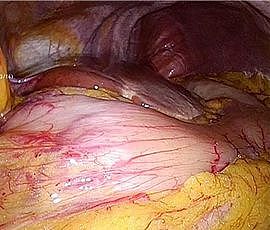

[胃がん] 手術:腹腔鏡下胃全摘術

手術画像